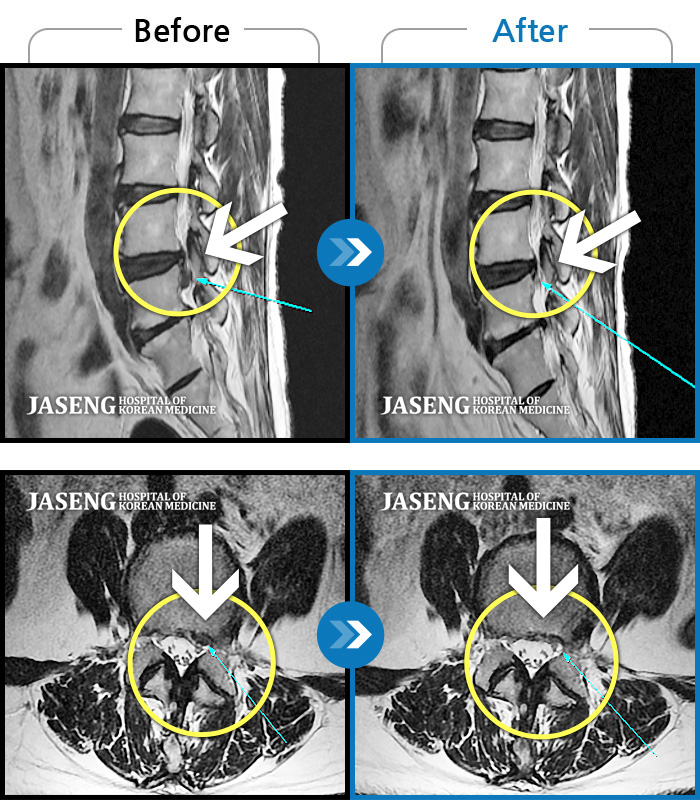

평소 거북목이어서 조심스럽게 생활하는 편입니다만, 체력이 떨어지거나 자칫 무리해서 물건을 들다보면 어쩔수 없이 병원 신세를 지게 됩니다.

3일전부터 목이 뻣뻣해지고 불안하다 싶더니, 결국 마트에서 장을 보고 옮기는 과정에서 '타닥' 소리와 함께 목을 못 가누게 되었습니다. 그날 집에 어찌 왔는지 기억도 없습니다. 밤에 아픈 쪽으로 누워 압통으로 잠을 청해보았지만(반대편은 근육이 늘어나는 고통으로 절대불가) 너무 아파서 밤을 꼴딱 새웠습니다. 아침에 주섬주섬 옷을 입고 병원에 가긴가야 하는데, 어디로 가야하나... 다니던 정형외과는 쌤이 다 바뀌셨고, 응급실로 가자니 전공의 파업으로 대기만 40명이 넘는다하고... 실패없이 최단시간 이 문제를 해결해 줄 곳. MRI 자료가 있고, 병력이 있어 망설임 없이 치료가 가능한 유능한 쌤이 있는 곳.

내원전 심한 어깨통증으로 걷지도, 앉지도, 아픈 쪽으로 눕지도 못하고 자다 깨곤했습니다. 내원후 x-ray , MRI 촬영, 목디스크 판정받았습니다. 추나+약침치료+청파전(환약+물약)복용으로 일상생활을 무리없이 하고 있습니다. 예후가 예상보다 빠르고 정확해 만족스럽습니다. 뼈, 관절, 근육관련 재방문의사 있습니다. 진원장님 그간 고생하셨습니다.